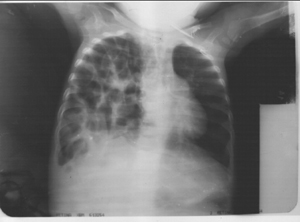

What is the diagnosis?

Chest radiograph reveals an anterior parasternal hernia with multiple air filled spaces with haustrations suggestive of intestinal loops within the right hemi-thorax suggestive of Congenital diaphragmatic hernia {CDH}. It is characterized by an incomplete formation or fusion, muscularization of the diaphragm resulting in apparent absence of the diaphragm or eventeration. The three basic types of CDH include the posterolateral Bochdalek hernia {occurring at approximately 6 weeks gestation}, the anterior Morgagni hernia and the hiatus hernia. Cryptogenic congenital diaphragmatic hernias has been a cause of sudden deaths in the early months of life. Mortality is significant at 50 percent depending on the other associated malformations. Associated high mortality rates which have not improved significantly despite advanced novel aggressive intensive perinatal and infantile interventions, are related directly to co-existent pulmonary hypoplasia or intractable persistent pulmonary hypertension, which are usually recalcitrant. Advanced novel therapies for CDH have included delayed operation, extracorporeal membrane oxygenation {ECMO}, high frequency oscillatory ventilation {HFOV}, surfactant ,and inhaled Nitric Oxide {INO} therapy. However,the effects of these modalities in terms of proffering a statistically significant survival advantages in neonates with CDH have not

been clearly determined. Surgical intervention of these defects is almost always indicated. This child in addition had hepatitis and multicystic kidney.